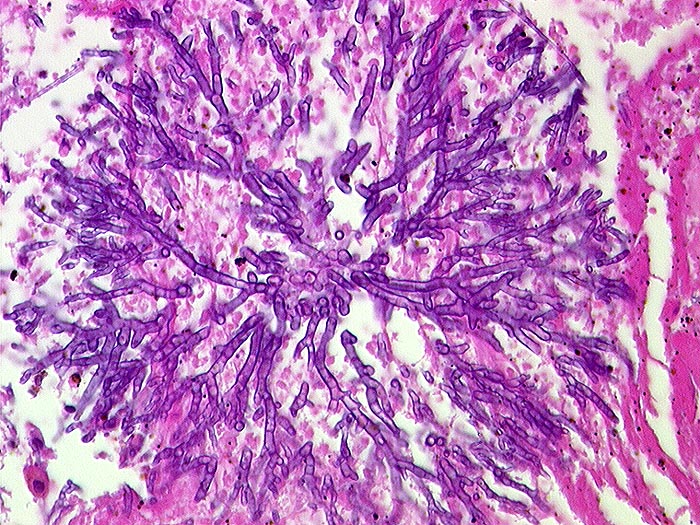

n/ Aspergillus

Aspergillus

Aspergillen gehören in die Gruppe der Schimmelpilze und wachsen ubiquitär auf organischen Stoffen. Der Erreger ist charakterisiert durch echte septierte Hyphen von 3 bis 6 Mikrometer Durchmesser. Die Hyphen verzweigen sich in einem Winkel von 45 Grad. Selten sind auch die (> 10851) (> 10849) Fruchtköpfe (Conidiophoren) nachweisbar. Aspergillusinfekte manifestieren sich je nach Resistenzlage als Aspergillom, invasive Aspergillose oder allergische Aspergillose. Der Nachweis von Aspergillus beweist noch nicht eine klinisch relevante Infektion.